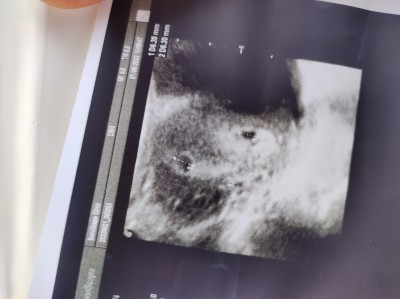

Merhaba kizlar bugun doktora gittim ikiz gebelik dediler sizde bakabilirmisiniz ikiz gebelikmi

image

Gebelik haftası 5

Aynn iki bebek görünüyor hayırlı olsun ;)

Zaten doktor ikiz gebelik demiş ilerleyen haftalarda belli olur şuan iki kese görünüyor ilerleyen haftalarda ne olur doktorunuz bilgilendirir hayırlı olsun

Hayırlı olsun İkiz gebelik bendede böyle 2 kese görünmüşdu